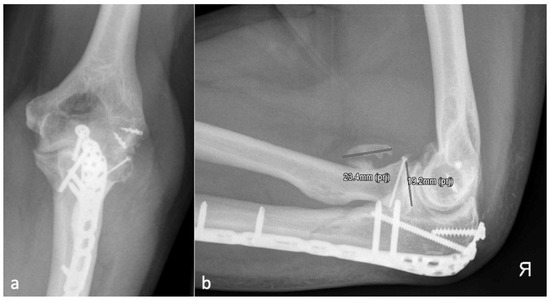

Figure 5.

(a) shows the AP and (b) shows the lateral X-ray with a brace formation radio-ulnar and represents an HO 4.